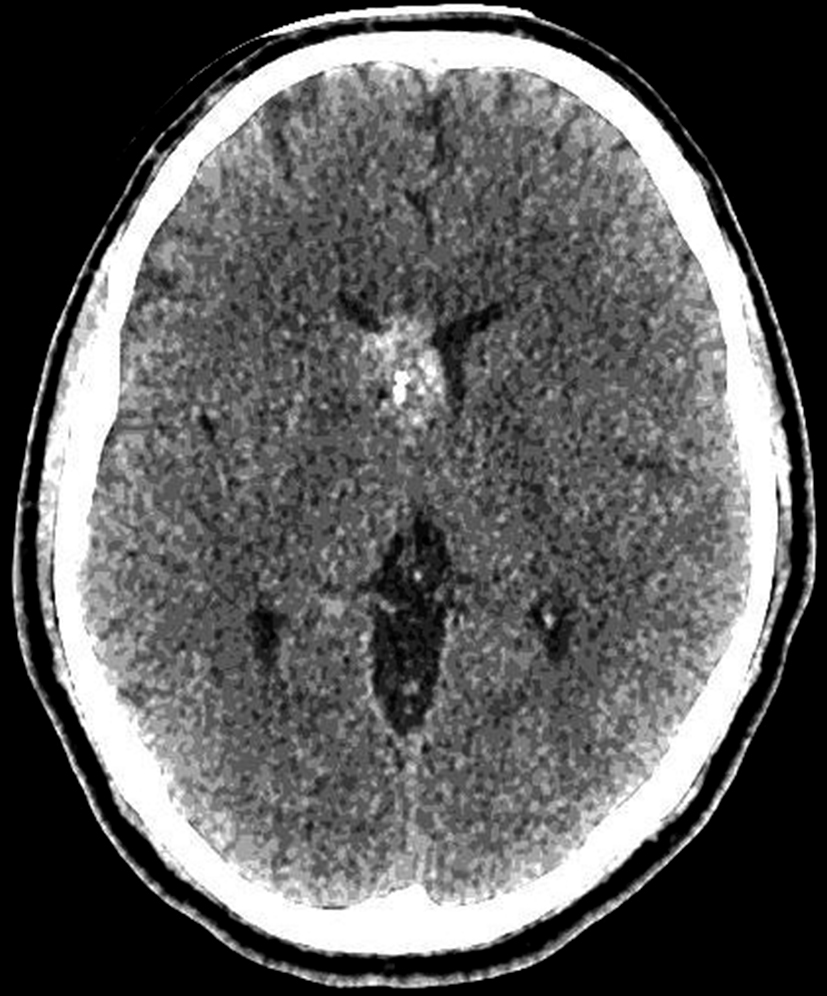

Con los hallazgos tomográficos, no se efectúan planteos diagnósticos y se realiza una resonancia magnética con la finalidad de obtener más datos semiológicos en busca de una aproximación diagnóstica. Se realizó el estudio por medio de secuencias T 1, FSE T 2, FLAIR, SWI y Difusión, en cortes axiales, FSE coronal y sagital T 1. Se realiza la administración de gadolinio DTPA en los tres planos. Se evidencia la lesión bien definida a nivel del ventrículo lateral derecho, que involucra al tronco del cuerpo calloso (Figura 2- C y 3- B). Presenta intensidad de señal heterogénea en secuencias T1 y T2 (Figura 3 y Figura 4). En secuencia ecogradiente se observa una señal marcadamente hipointensa y heterogénea, con un halo hipointenso bien definido (Figura 2- C). No presenta realce significativo tras la administración de Gadolinio (Figura 2- B) y en la secuencia de difusión no presenta restricción.

Figura 2 Resonancia magnética.

a) Imagen axial T1, lesión intraventricular con intensidad de señal heterogénea.

b) Tras la administración de Gadolinio no presenta realce significativo.

c) Imagen axial en secuencia ecogradiente donde se evidencia la lesión hipointensa y heterogénea. Se observa la extensión de la lesión al cuerpo calloso.

La RM es la herramienta diagnóstica de elección. En la RM es una lesión bien definida con intensidad de señal heterogénea en secuencias T1 y T2 resultante de trombosis, fibrosis, calcificación y hemorragia. La metahemoglobina extracelular e intracelular y la trombosis son responsables de la alta señal de intensidad dentro de la lesión, mientras que las calcificaciones, fibrosis y sangre subaguda son responsables de las áreas de baja señal (5). En la secuencia ecogradiente, se evidencia la lesión heterogénea, predominando los sectores hipointensos debido al efecto de susceptibilidad magnética, con un anillo periférico hipointenso que corresponde al depósito de hemosiderina y hierro en el parénquima cerebral circundante. El anillo de hemosiderina puede no ser evidente en el cavernoma intraventricular (1,3,5). El cavernoma es una malformación angiográficamente oculta, debido a su pobre conexión con el sistema vascular y la angiografía cerebral raramente muestra anormalidades (1,3,4,5).

Los diagnósticos diferenciales incluyen otras lesiones intraventriculares como: el meningioma, el ependimoma, astrocitomas de bajo grado o papiloma del plexo coroideo (2). La falta de edema circundante en imágenes FLAIR o T2, la hemosiderina periférica y la falta de realce hacen que el tumor sea menos probable y favorecen la malformación vascular atípica. Pero en la RM, la hiperintensidad central, debido a la metahemoglobina y el borde de hemosiderina periférica, limita los diferenciales. El realce del contraste no ayuda mucho en la diferenciación y la secuencia ecogradiente puede ser extremadamente útil (5).